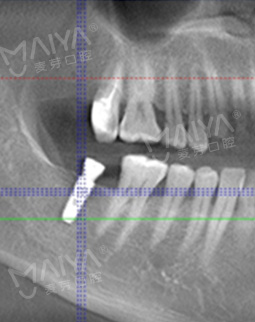

拍了片子,医生指出牙周膜增宽,左上根尖部阴影大,面部有稍微萎缩,为我制定了数字化精确种牙技术,其实也很好奇,现在种牙到底有多精确多快速,和医生约定好了时间,下次直接种牙。